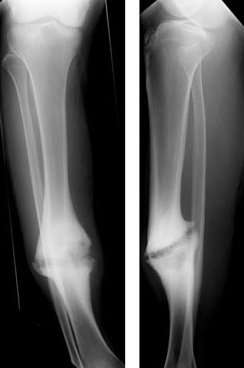

| Hypertrophic nonunion of the tibia | |

Pseudarthrosis (commonly referred to as a nonunion or false joint) is a bone fracture that has no chance of mending without intervention. In pseudarthrosis the body perceives bone fragments as separate bones and does not attempt to unite them. Often this is the result of inadequate healing after the fracture, though it can also be the result of a developmental failure. In the U.S., FDA guidelines allow a period of 9 months for fracture union, after which intervention is considered to facilitate union.

The Greek stem "pseudo-" means false and "arthrosis" means joint. Pseudarthrosis, then, is a false joint. In the case of a "non-union", a fracture that does not heal, this is often evidenced by the obliteration of the medullary cavity of a long bone at the site of the non union. This non union is not a true joint, and has no ligamentous support, but often has motion, and remodels into a rounded end that looks like a true joint.